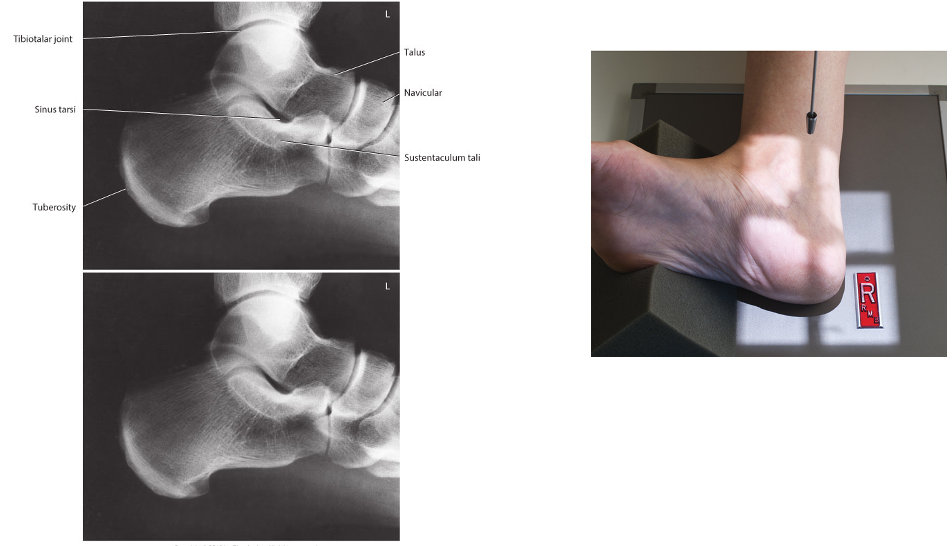

Lateral Calcaneus

• IR 8x10 portrait, 40 SID

• Pt in seated or lateral recumbent position. Place uninjured leg behind injured. Center calcaneus to CR and IR with long axis of foot parallel to plane of IR. Support knee and leg as needed to place plantar surface parallel to IR. Dorsiflex foot so plantar surface is at a right angle to leg

• CR perpendicular to IR, directed to a point 1” inferior to medial malleolus. Collimate to include distal ankle joint and all of calcaneus.